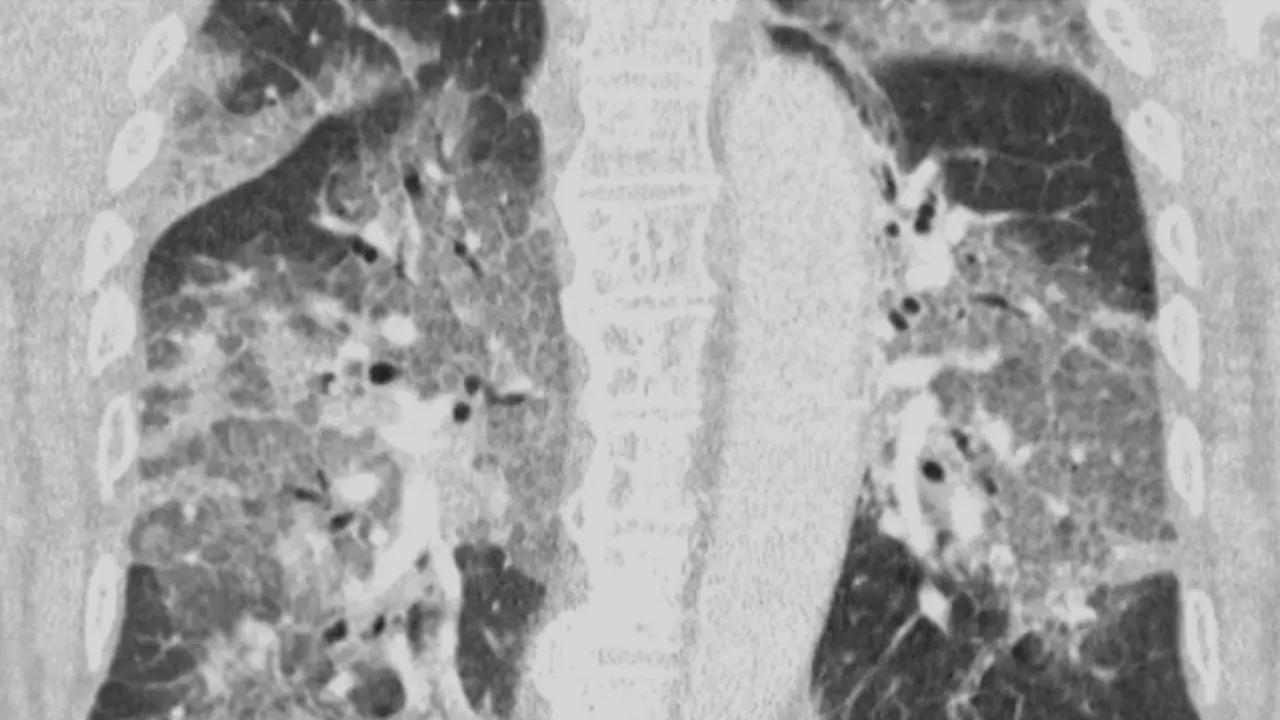

Descubren un nuevo fármaco que puede salvar la vida a un tercio de los pacientes graves de Covid Redacción 17/06/21